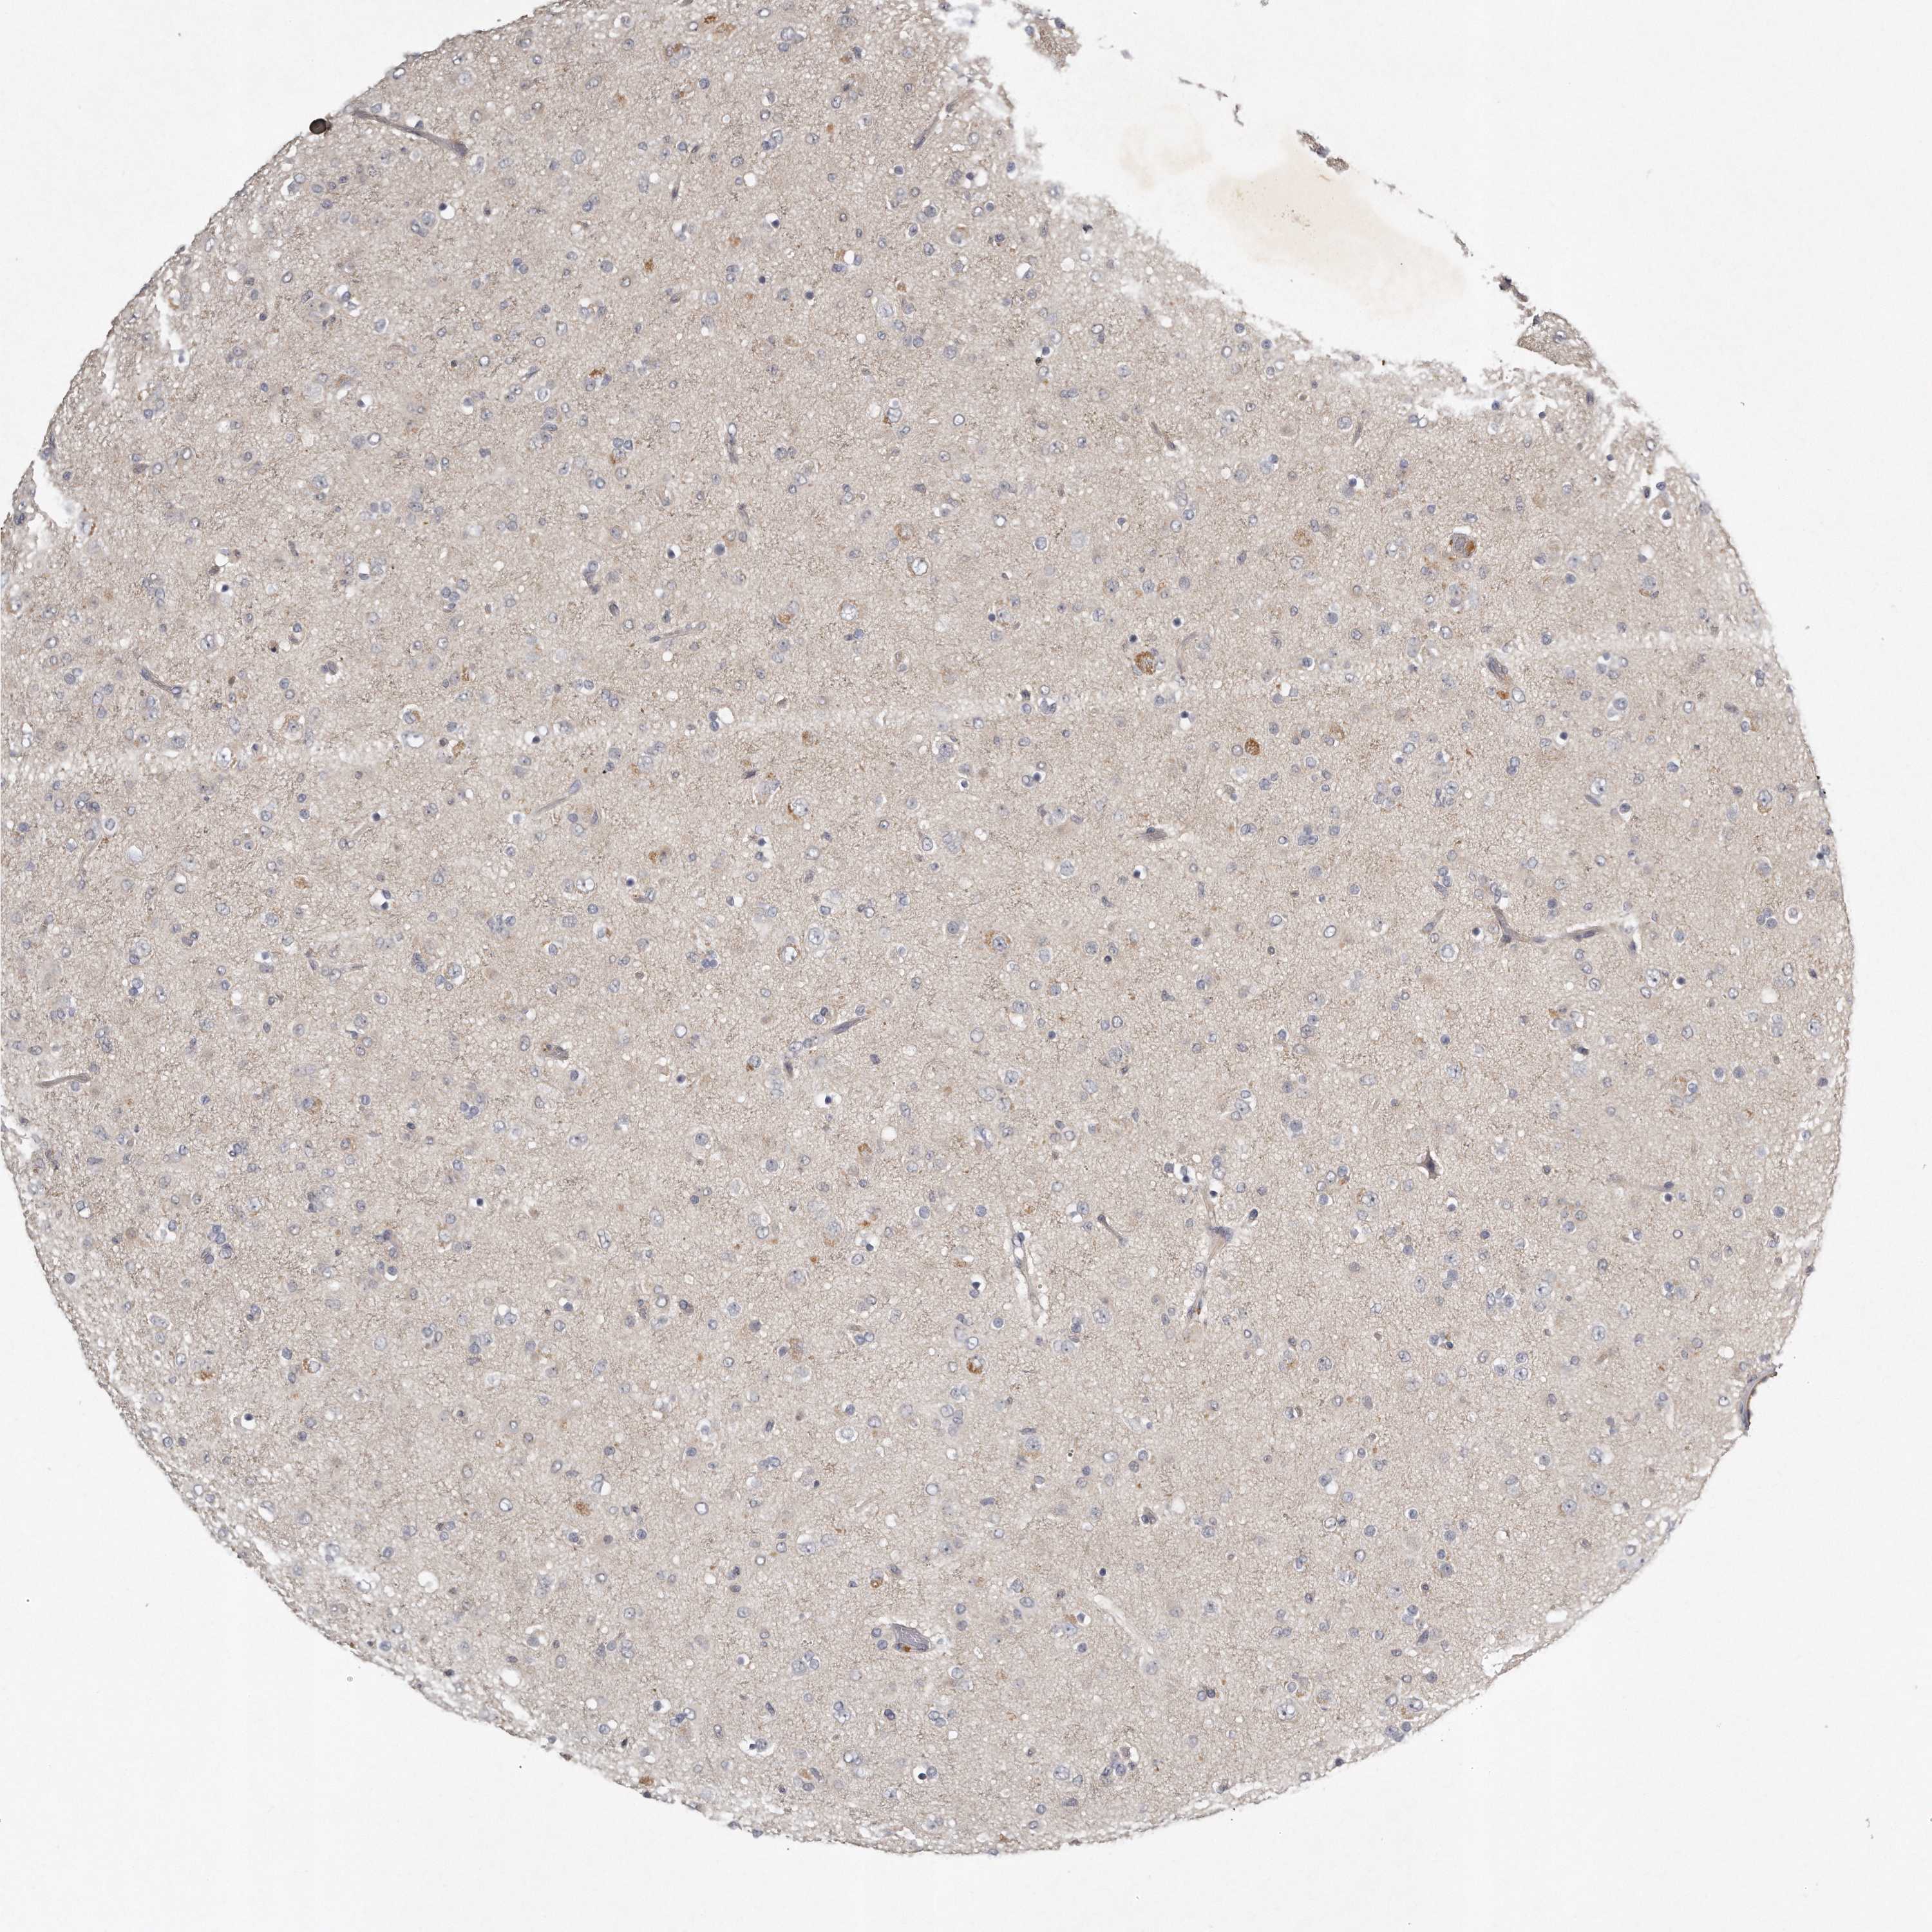

GLIOMA - Protein expressioni

A mouse-over function shows sample information and annotation data. Click on an image to view it in a full screen mode. Samples can be filtered based on level of antibody staining by selecting one or several of the following categories: high, medium, low and not detected. The assay and annotation is described here.

Note that samples used for immunohistochemistry by the Human Protein Atlas do not correspond to samples in the TCGA dataset.

Antibody stainingi

Antibody staining in the annotated cell types in the current human tissue is reported as not detected, low, medium, or high, based on conventional immunohistochemistry profiling in selected tissues. This score is based on the combination of the staining intensity and fraction of stained cells.

Each image is clickable and will lead to virtual microscopy that enables deeper exploration of all samples and also displays staining intensity scores, fraction scores and subcellular localization as well as patient and tissue information for each sample.

Antibody HPA020735

Antibody HPA029914

Staining

High

Medium

Low

Not detected

Intensity

Strong

Moderate

Weak

Negative

Quantity

>75%

75%-25%

<25%

None

Location

Nuclear

Cytoplasmic/membranous

Cytoplasmic/membranous,nuclear

Glioma, malignant, High grade

Glioma, malignant, Low grade

Glioblastoma, NOS